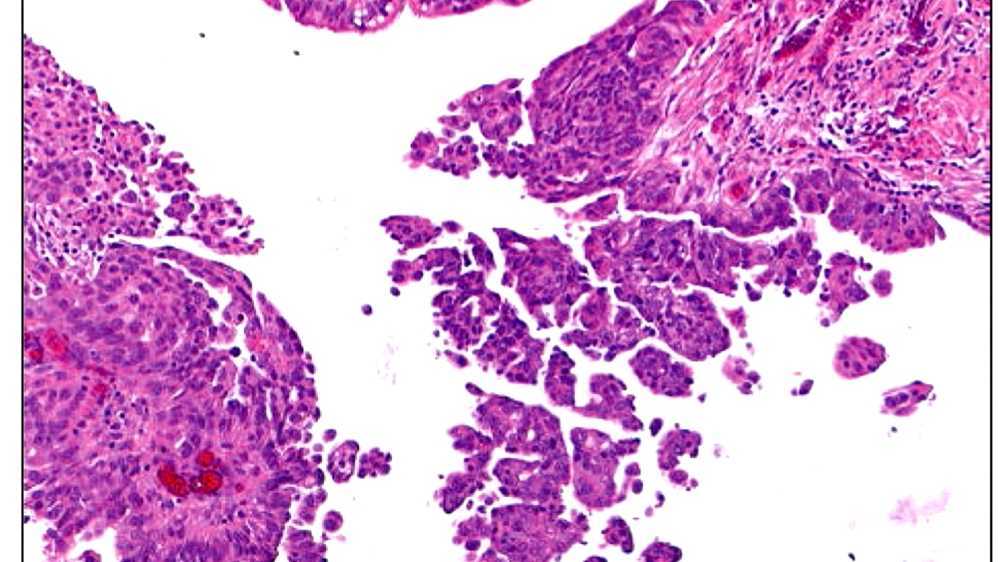

Primary peritoneal cancer or carcinoma is also known as surface serousis papillary carcinoma, primary peritoneal carcinoma, extra-ovarian serous carcinoma, serous primary papary carcinoma, psammomacarcinoma. It has historically been classified under "primary carcinoma unknown" (CUP). Primary peritoneal cancer (PPC, or PPCa) is a cancer of cells that line the peritoneum, or abdominal cavity.

Histomorphological and molecular biological characteristics indicate that serous carcinoma, which includes ovarian serous carcinoma, serous carcinoma of the uterus, Fallopian tube serosal carcinoma, serous carcinoma of the cervix, and primary serous peritoneal carcinoma actually represent one entity.